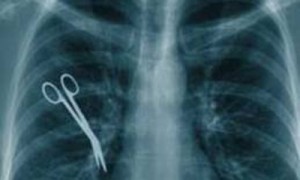

Законопроект разработан в целях защиты прав пациентов от врачебной ошибки. Он обязывает все медорганизации страховать свою ответственность перед пациентами. В соответствии с законопроектом, в случае смерти пациента размер страховой выплаты составит 2 миллиона рублей, в случае наступления инвалидности I группы – 1,5 миллиона рублей, II группы – 1 миллион рублей, III группы – 500 тысяч рублей.

Предполагается, что устанавливать факт врачебной ошибки и расследовать обстоятельства будут специальные комиссии в составе от 7 до 11 человек. Они будут работать на общественных началах. В них будут входить представитель территориального органа исполнительной власти, представитель главного бюро медико-социальной экспертизы по соответствующему субъекту РФ, представитель органа управления здравоохранением субъекта РФ; представитель организации по защите прав граждан в сфере охраны здоровья граждан; представитель профессиональных общественных объединений медицинских работников.